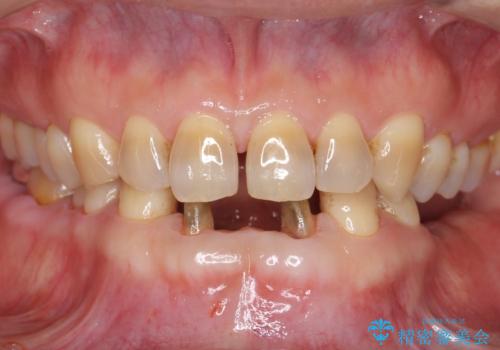

- 前歯の保険のブリッジが欠けてしまっているのを治したいとのことでした。

前装冠が剥がれていて、下の金属が見えてしまっていました。

保険のブリッジは入れてすぐ欠けてしまったのを長年使用していたとのことです。